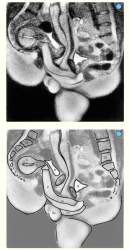

思ったより曲がっている…

性交中および女性の性的興奮時の男性および女性の性器のMRI

https://pmc.ncbi.nlm.nih.gov/articles/PMC28302/

P=penis Ur=urethra(尿道) Pe=perineum(会陰) U=uterus(子宮) S=symphysis(恥骨結合) B=bladder(膀胱) I=intestine(腸) L5=lumbar 5(腰椎) Sc=scrotum(陰嚢)

正常位でもちゃんと子宮が下側に来るんだな

Figure 2の形になるもんだと思ってた

>正常位でもちゃんと子宮が下側に来るんだな

>Figure 2の形になるもんだと思ってた

正常位だから背中側に落ちるのかも